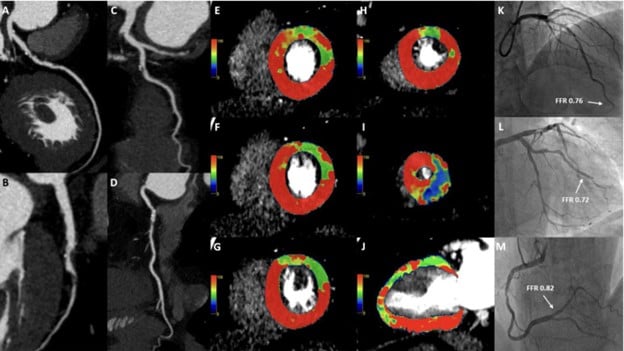

Deep Learning Enables Dual Screening for Cancer and Cardiovascular Disease